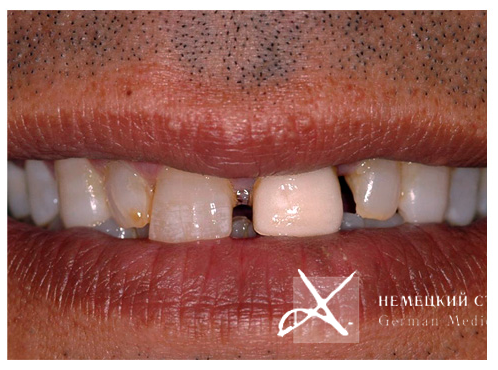

Пациент (45 лет) обратился в клинику с целью закрытия свободных пространств (промежутков) между зубами без ортодонтического вмешательства.

Выполнено эстетическое протезирование коронками на основе оксида циркония с эффектами на основе принципов иллюзорного восприятия, позволяющими скрыть ширину между зубами.